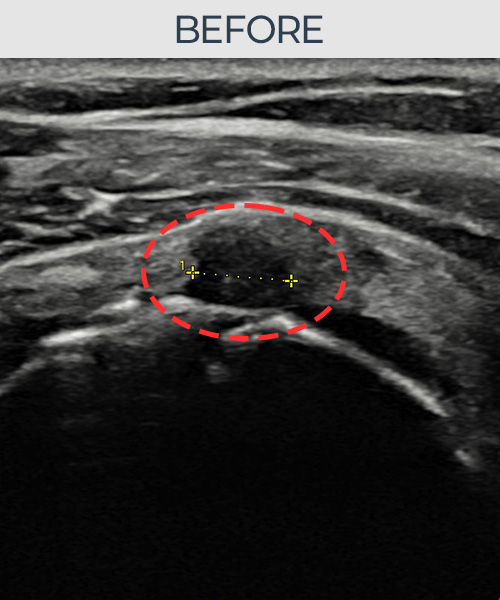

김ㅇㅇ님 · 좌측 극상근건 부착부 광범위 부분파열

좌측 어깨 극상근건 광범위 파열로 수개월간 일상생활이 어렵던 중 내원하셨습니다. 초음파 검사에서 부착부 광범위 부분파열이 확인되었으며, 어깨인대 축소봉합술 시행 후 힘줄 구조가 회복되었습니다.